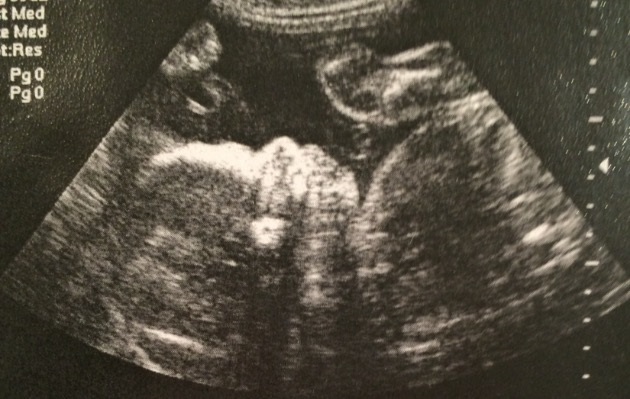

WOW!  Time flies.   It’s hard to believe that little face you see there is 10 years ago.  I think the whole time of being pregnant felt longer in the last couple of months than the last 10 years have.  Where does time go… I was one of those girls who...